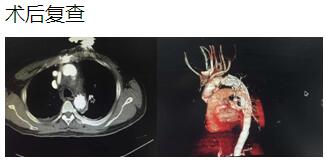

通訊員 李小升 報道:近日,衡陽市中心醫(yī)院心胸外科成功完成一例淺低溫停循環(huán)下“孫氏手術(shù)”(升主動脈置換、主動脈弓置換、降主動脈術(shù)中支架置入)。

患者是一位48歲中年男性,因胸痛1小時入院,我院CT提示主動脈夾層累及胸、腹主動脈全層,診斷為主動脈夾層(D ebaKey I型)?;颊卟∏槲V兀中g(shù)治療是挽救其生命的唯一希望。為了挽救病人生命,經(jīng)過麻醉科、手術(shù)室、體外循環(huán)組的術(shù)前充分討論,心胸外科廖金文主任、廖承輝副主任帶領(lǐng)團隊決定為其施行復(fù)雜而高難度的淺低溫停循環(huán)下“孫氏手術(shù)”。術(shù)中見主動脈全程及三分支受累,右冠受累,冠脈開口受壓狹窄,予以行“升主動脈 主動脈弓置換 降主動脈術(shù)中支架置入術(shù)”,團隊成員歷經(jīng)約10個小時的奮戰(zhàn),手術(shù)順利完成。術(shù)后六小時患者意識完全清醒,現(xiàn)在已完全康復(fù)。